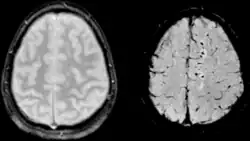

Diffusion weighted imaging offers a powerful means to detect acute stroke. Although it is well known that gradient echo imaging can detect hemorrhage, it is best detected with SWI. In the example shown here, the gradient echo image shows the region of likely cytotoxic edema whereas the SW image shows the likely localization of the stroke and the vascular territory affected (data acquired at 1.5 T).

The bright region in the gradient echo weighted image shows the area affected in this acute stroke example. The arrows in the SWI image may show the tissue at risk that has been affected by the stroke (A, B, C) and the location of the stroke itself (D). The reason that we are able to see the affected vascular territory could be because there is a reduced level of oxygen saturation in this tissue, suggesting that the flow to this region of the brain could be reduced post stroke. Another possible explanation is that there is an increase in local venous blood volume. In either case, this image suggests that the tissue associated with this vascular territory could be tissue at risk. Future stroke research will involve comparisons of perfusion weighted imaging and SWI to learn more about local flow and oxygen saturation.